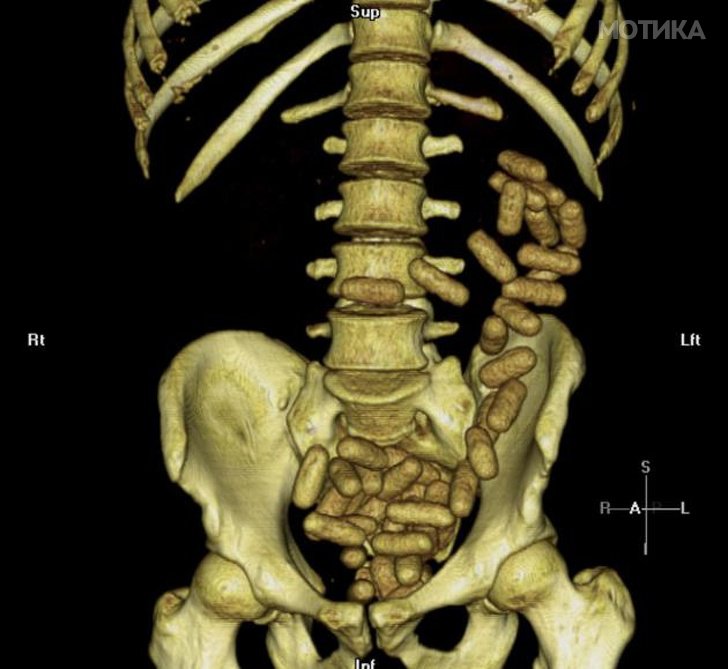

9. МР на абдоминалната празнина на курир кој е фатен како пренесува забранети супстанции